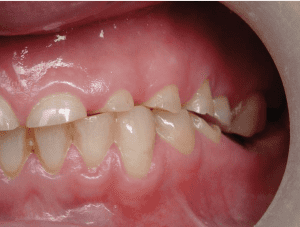

שחיקת השיניים שכשמה כן היא, נגרמת מפעילות לא רצונית של שרירי הלעיסה שמזיזים את הלסתות, תוך הפעלת כוחות חזקים ביותר, שגורמת לשחיקה והרס מוגבר של חומר השן.

במקרים קיצוניים, יכולה כל כותרת השן להשחק עד לגובה החניכיים.

• הרס רב של חומר שן

• שברים וסדקים בשיניים

מקרה 1

שחיקת שיניים